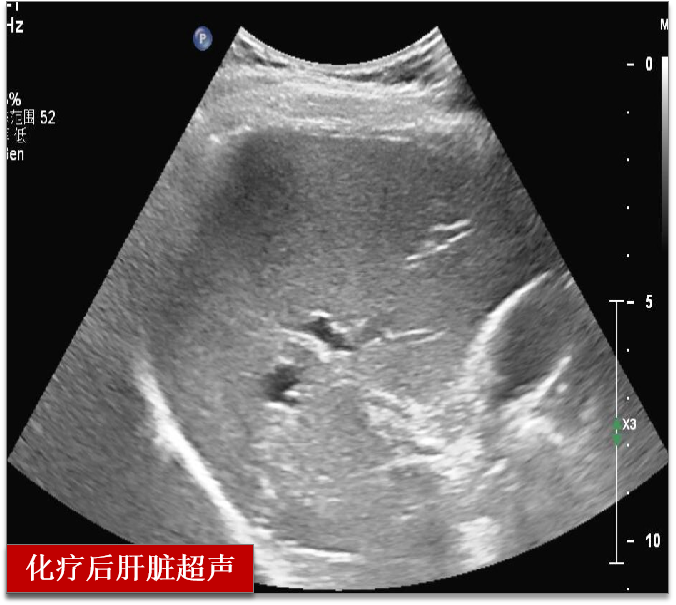

两个周期的化疗后

超声检查提示肝脏肿瘤完全消失

乳房肿瘤较前缩小